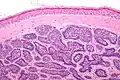

Micrograph of dermal cylindroma in H&E stain. -

Dermal cylindromas are:

- Dermal lesions consisting of nests of cells that are surrounded by hyaline (i.e., glassy, eosinophilic, acellular) material and have:

- Hyperchromatic nuclei that may palisade (columnar nuclei arranged around the periphery of the cell nests with their short axis tangential to the nest periphery), and

- Cells with lighter staining ovoid nuclei at their centre.

They lack of a significant number of lymphocytes; this differentiates them from spiradenomas.